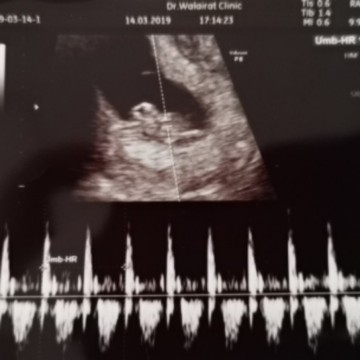

ตอน12สัปดาห์ค่า

7วีค5วันคะ